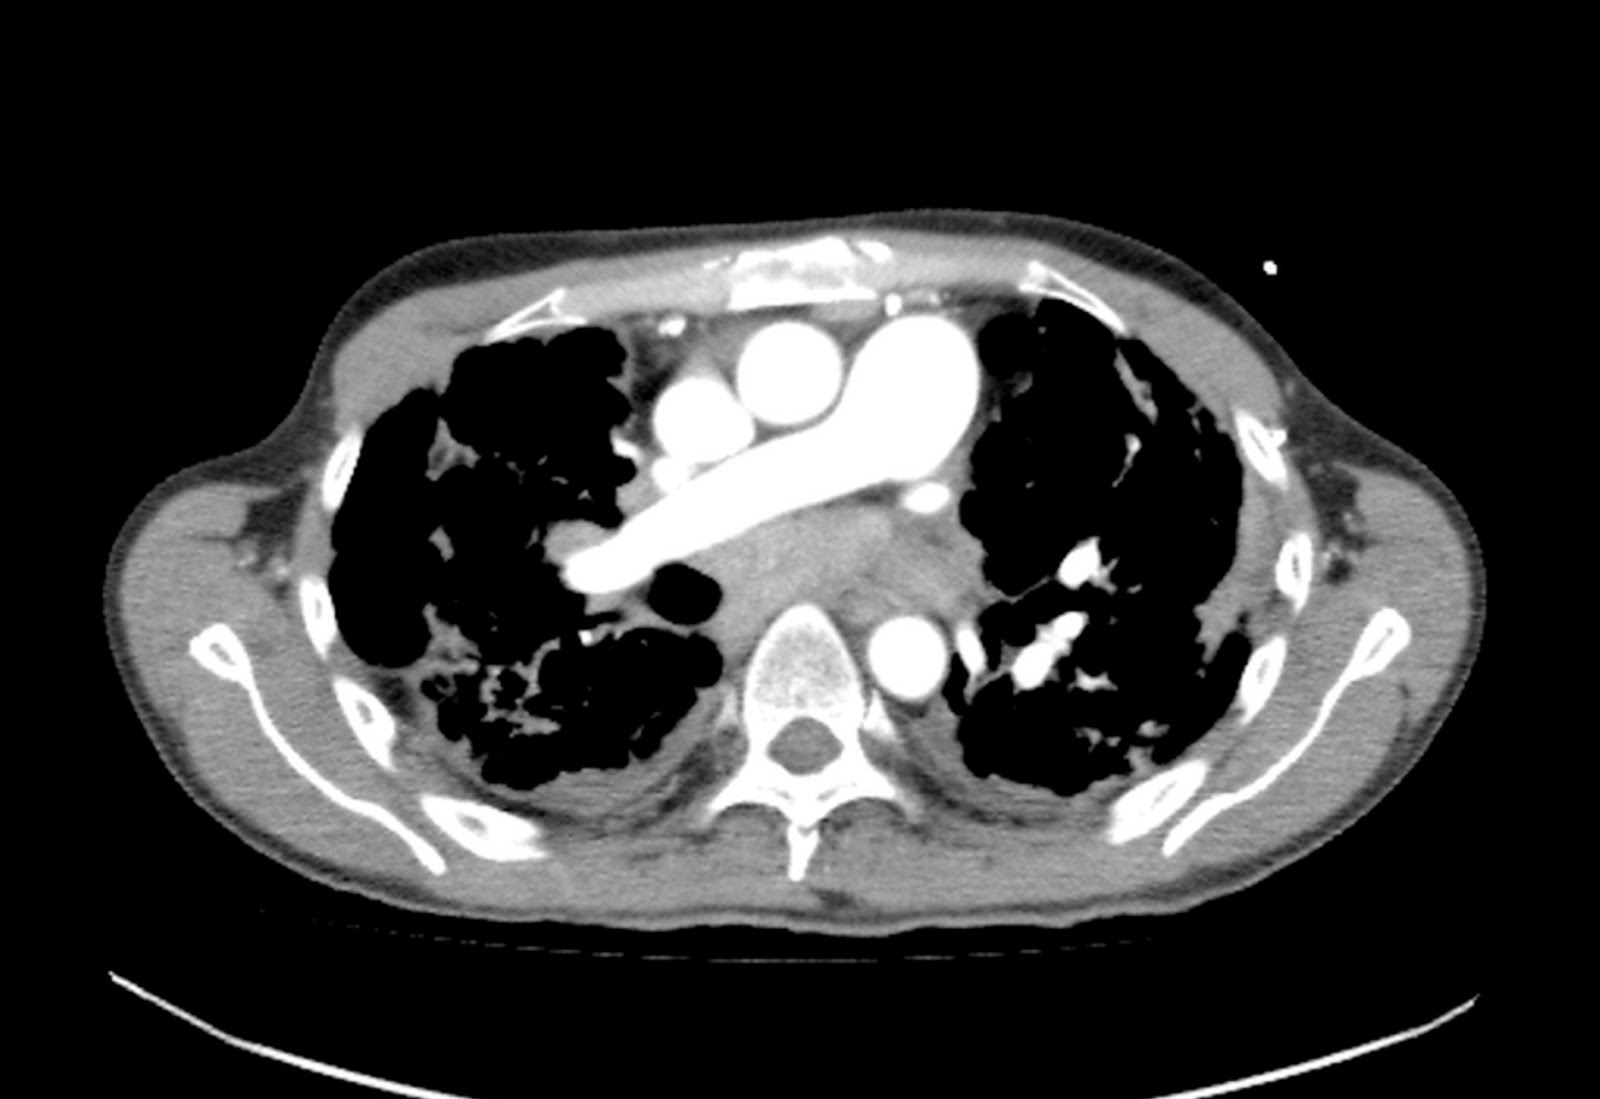

Hombre de 61 años asintomático. Colonoscopia demuestra válvula ileocecal ulcerada y estenótica. No hay antecedente de Enfermedad Inflamatoria Intestinal.

Con base en lo anterior el siguiente paso a seguir es?

a) Valoración por cirugía general.

b) Iniciar tratamiento con anti-inflamatorios e inmunosupresores.

c) Biopsia bajo guía ecográfica de las lesiones focales hepáticas.

d) Repetir colonoscopia.